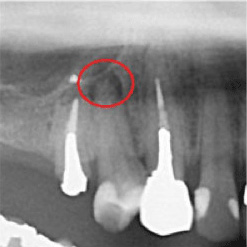

当院で処置した症例をご紹介します。

他院で抜歯と言われてしまった歯でも抜歯せずに対処した症例も多数あります。

黒い影が出ている部分が問題の個所で(根尖病巣)、治療後はこの影がなくなっているのが見て取れると思います。

保険適用。根尖病巣を治療した症例。リスクとして、稀ではありますが再発することがあります。